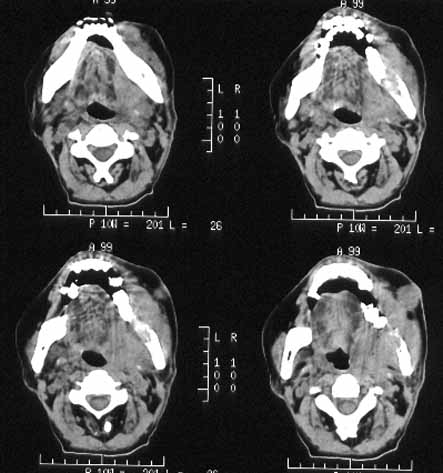

男性,60岁,鼻咽癌放疗后12年,5年前复发再行放疗后缓解。近期牙痛,牙龈活检见鳞癌细胞。

ct诊断:鼻咽癌复发,侵及左下颌骨、上颌骨及颞下窝。